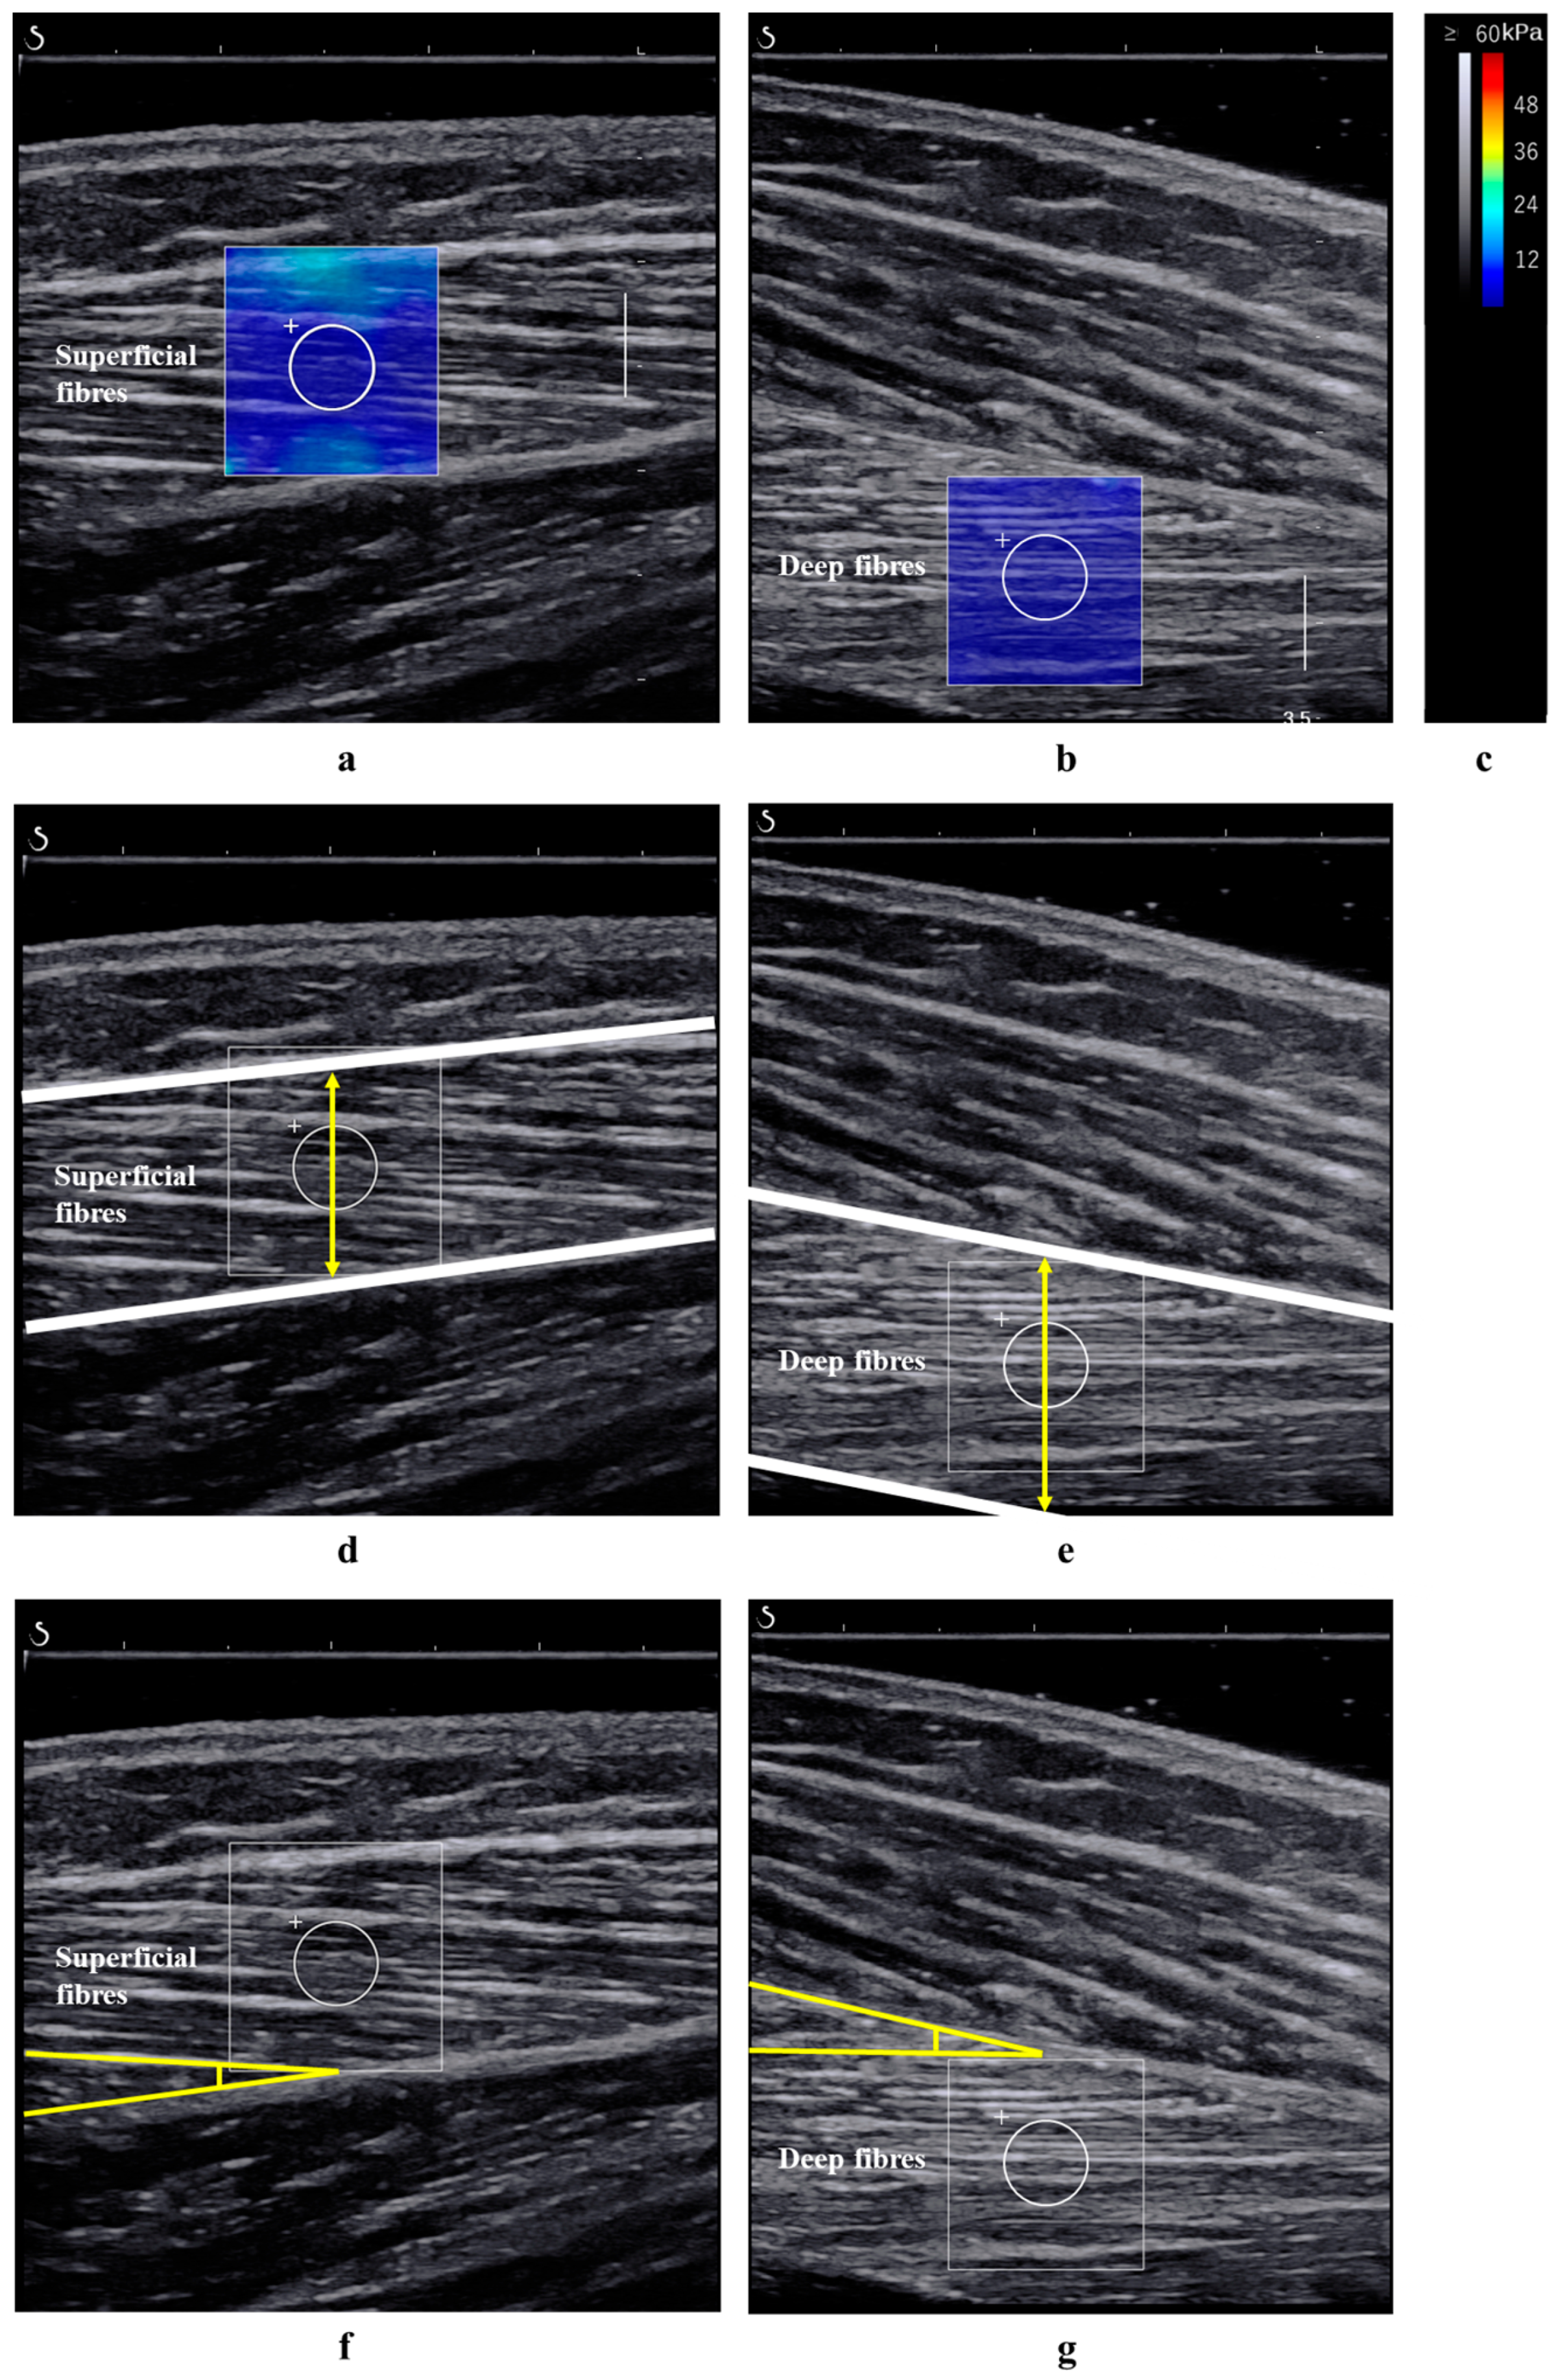

2.3. Measurement of the Shear Modulus and Architecture of the TA Muscle